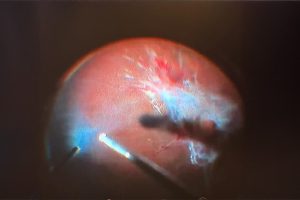

Retina Dekolmanı Neden Olur? - Sağlığa Dair | 8 Mart 2025